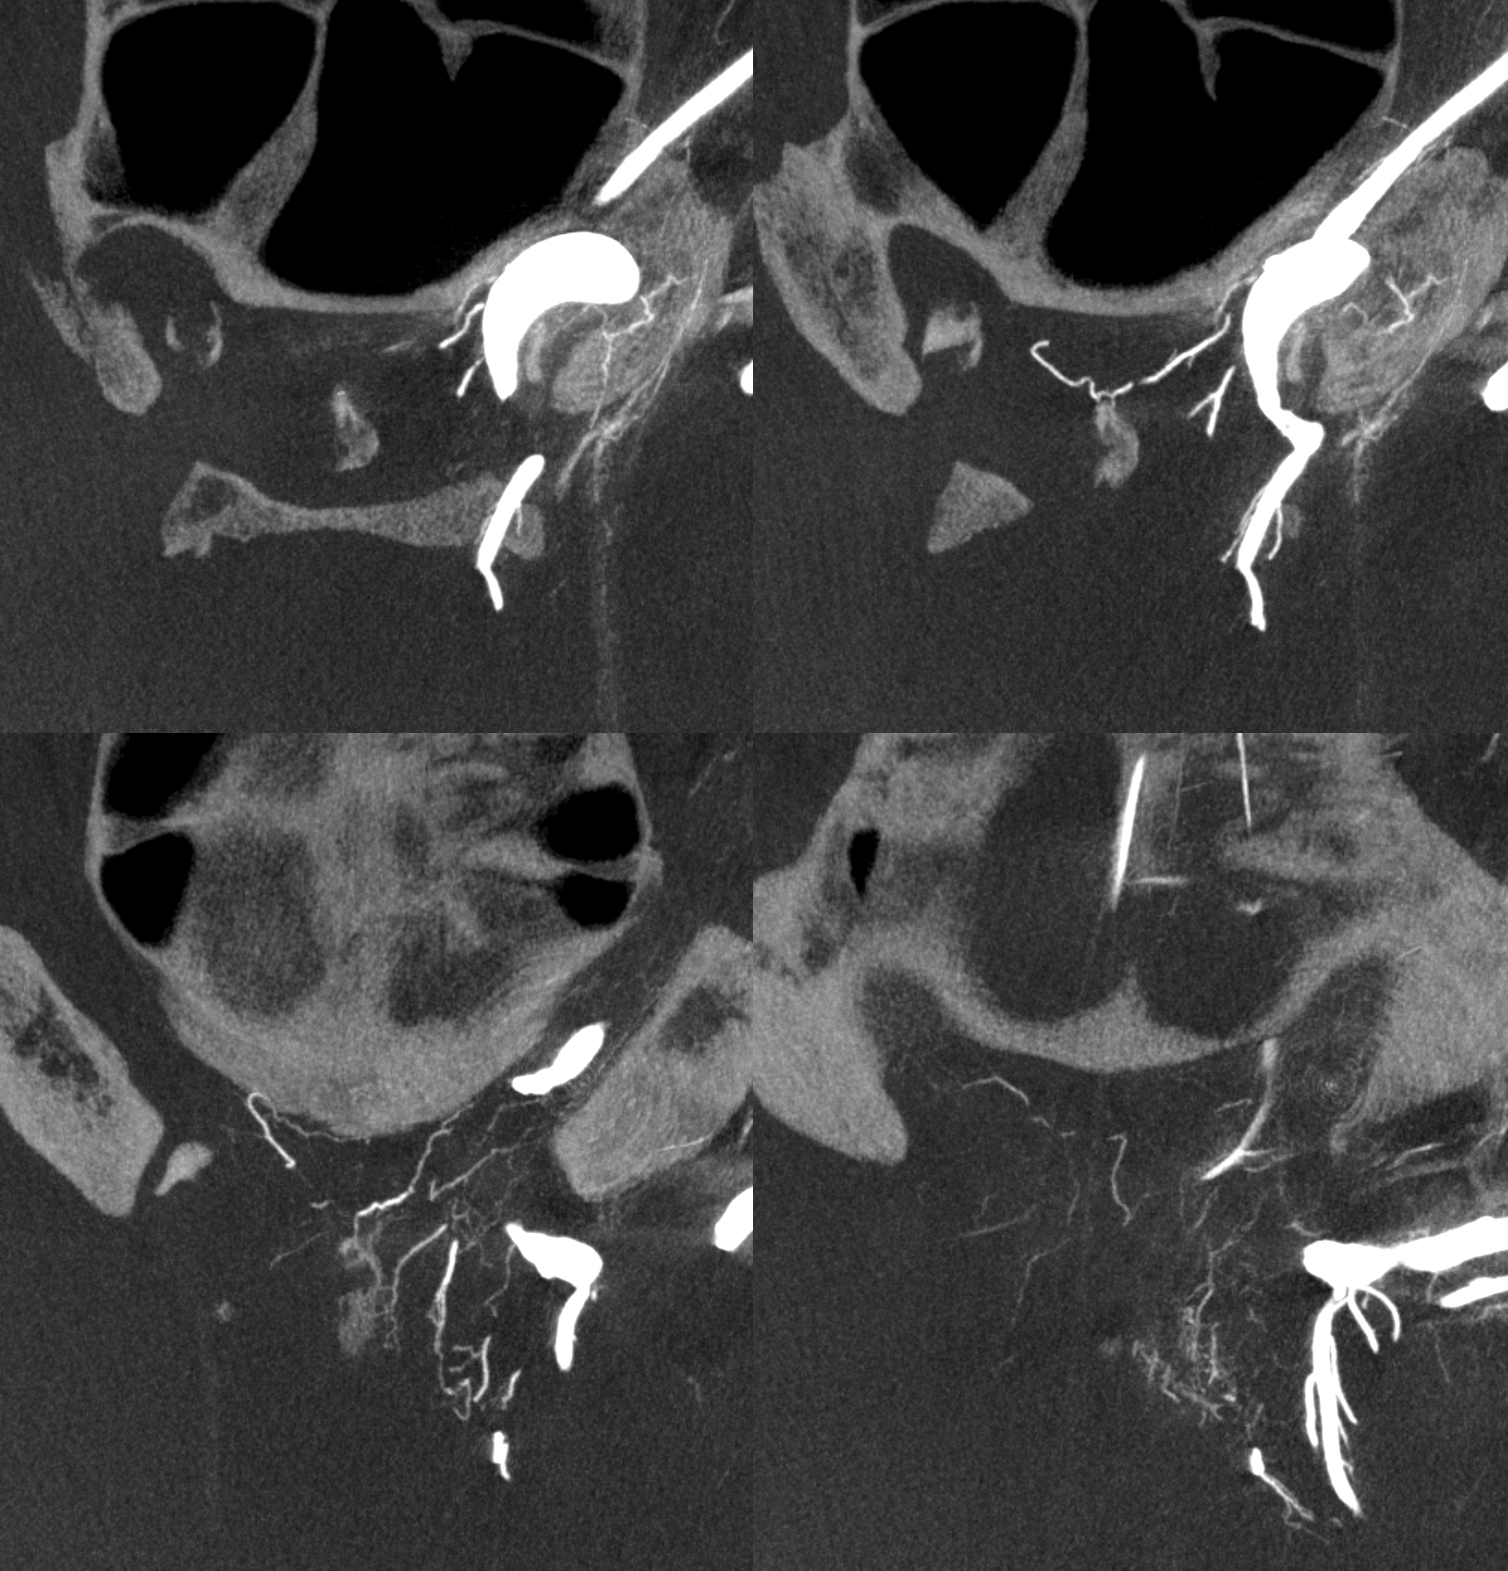

Stereos and MIPs. Both superior and inferior hypophyseals are well seen. The superior hypophyseal, despite being invisible on standard issue views, is quite large, even having two branches to the hypophysis.

Case courtesy Dr. Eytan Raz — here is a beautiful example of a very dominant superior hypophyseal artery (arrow) supplying the posterior hypophysis (arrowhead), with a correspondingly small inferior hypophyseal contribution from the MHT (dashed arrow)

Cross eye stereo

View from the back — again small inferior hypophyseal, big superior hypophyseal — balance again… See the beautiful vascular ring of the posterior pituitary — the connecting it with the contralateral side

Cross-eye stereo

MIP image shows the sella nicely — and helps prove its posterior pituitary

Pure arrowless images — easier to steal…

Of course, there is an aneurysm here — the branch point camp would point out how this larger than usual branch is a setup for aneurysmal formation. Naturally…